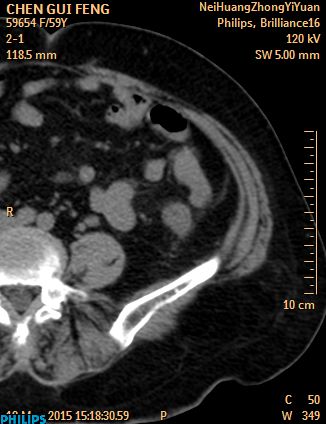

CT50085:小肠占位?

本帖最后由 cefcmj 于 2015-3-18 19:42 编辑 nhxzyy 病人女,左下腹疼痛,按压痛。 CT:左下腹小肠肠腔外见肿块影。

左下腹肠系膜脂肪炎

降结肠肠脂垂炎可能

周围脂间隙毛糙 考虑炎性 肠壁有点增厚了